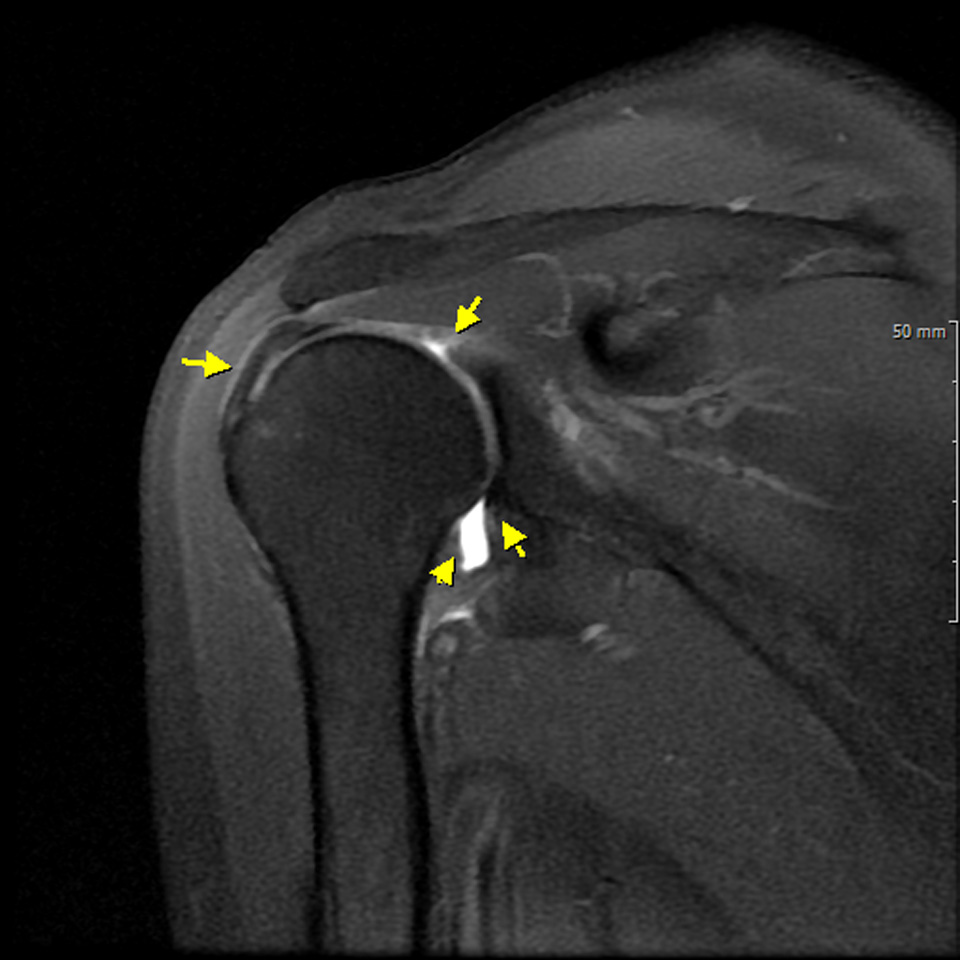

관절낭이 유착되는 질환이므로

MRI arthro 로 촬영해서 조영제가 투입되는

양이 적은 경우도 확인하는 것이 필요하다

관절 조영 MRI 영상검사에서 관절의 용적이 줄어서 관절 조영제가 적게 관찰된다.